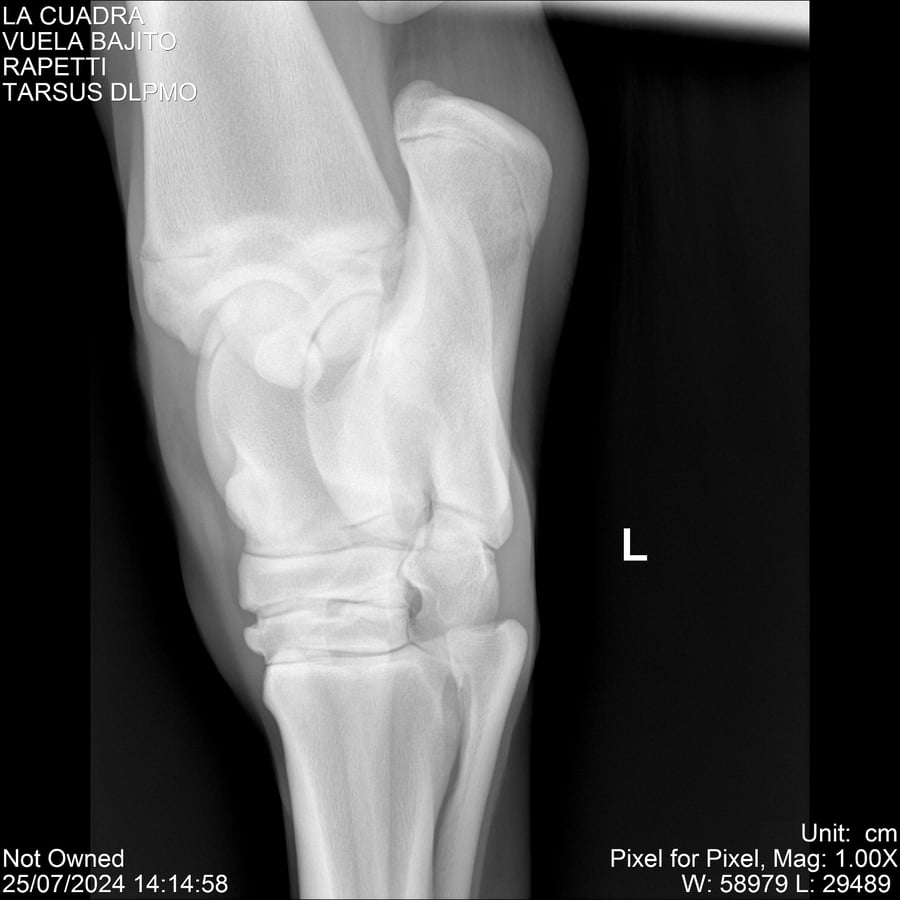

LOTE 16, VUELA BAJITO Lote Anterior Volver al remate Lote Siguiente Ficha Contacto Montevideo - Ficha del Lote Identificador: #284451 Categoría: Yeguarizos Montevideo - 77 Visualizaciones ClicData Contacto Empresa: Abelenda N. R., Walter Hugo Nombre*: Teléfono* : E-mail* : Mensaje Enviar Registrese gratis Este contenido Exclusivo está disponible sólo para usuarios registrados Ingresar